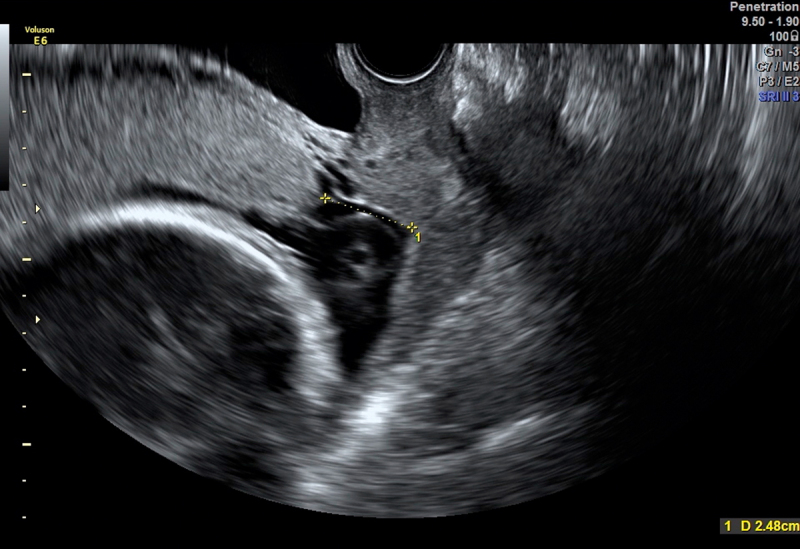

Persistent Funic Presentation And Sonographic Assesment Of The Risk For Umbilical Cord Prolapse.

脐带脱垂风险的持续绒毛表现和超声评估